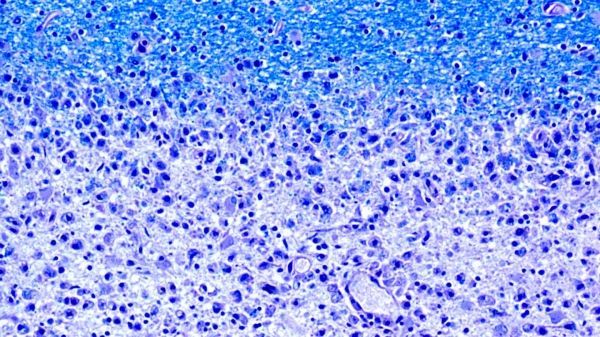

Image: Diminishing myelin sheaths: The damaged areas (at the bottom of the image) of the brains of MS patients lack myelin (at the top, in blue). (Image: Dr. med. Imke Metz, University of Göttingen, Germany) (Credit: Dr. med. Imke Metz, University of Göttingen, Germany)